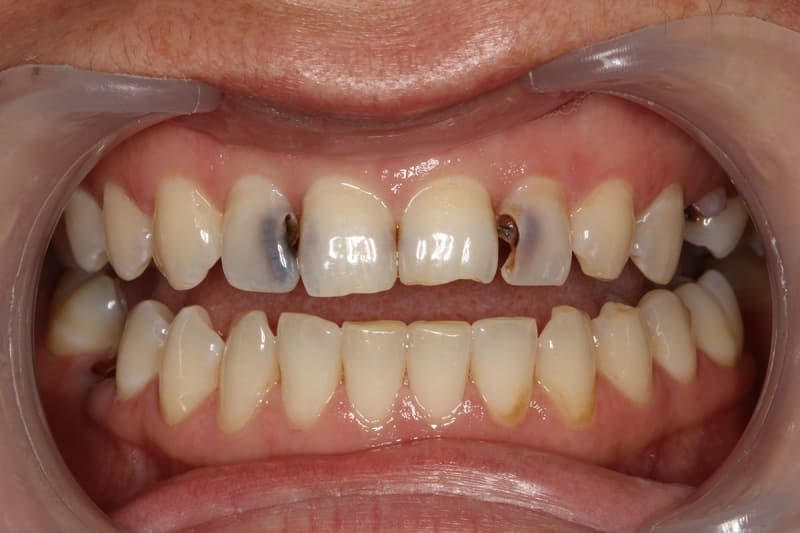

Развитие кариозных образований происходит постепенно, начиная с поражения эмали на поверхности зуба и распространяясь вглубь к корням зуба. Фотографии кариеса на разных стадиях его развития наглядно демонстрируют эти изменения.

На данном этапе кариес уже трудно не заметить, а игнорирование его лечения крайне опасно. Кариозные пятна на поверхности зубов значительно увеличиваются и их легко заметить самостоятельно. Однако есть случаи, когда зубы имеют достаточно прочную эмаль, чтобы устоять перед кариесом, и пятна не видны. В таких ситуациях, если есть трещина в эмали, кариес проникает внутрь зуба, поражая более мягкие ткани, известные как дентин. Кариес часто начинает проявляться на задней стороне зубов и между ними. Обычно кариозные образования сосредоточены глубже на поверхности и часто в области между зубами. Лечение в таких случаях включает очищение пораженной поверхности от налета и применение лекарственных средств в полости рта для уничтожения вредоносных бактерий. На место удаленной зубной ткани устанавливается пломба, которую необходимо регулярно очищать от образовавшегося налета.

В статье представлены фотографии, которые наглядно объясняют, какие повреждения может вызвать этое заболевание и что такое кариес зубов. Каждая последующая стадия болезни требует все большего вмешательства со стороны врача.